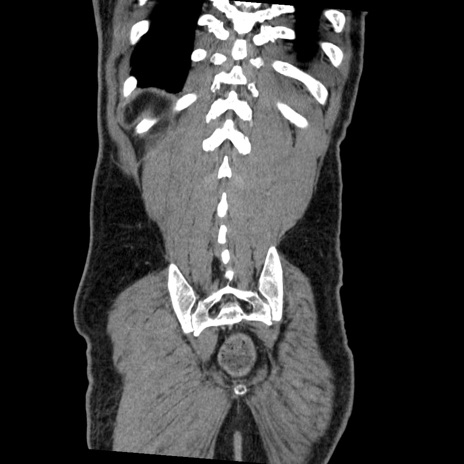

症例22(冠状断像)

【症例】50歳代男性

【主訴】腹痛

【現病歴】AVMからの被殻出血のため回復期リハ病棟入院中。 本日午後3時頃急に下腹部痛が出現した。

【既往歴】AVM、被殻出血、虫垂炎、高血圧

【身体所見】意識晴明、左半身不全麻痺、会話の理解は良好、36.5°C、腹部:膨隆、全体に板状硬、下腹部正中に圧痛点あり、反跳痛-、筋性防御不明、右下腹部にope scar

【データ】WBC 9400、CRP 0.06